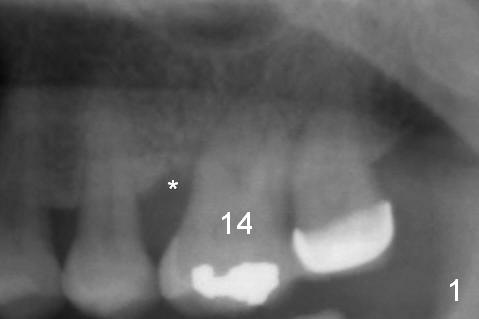

A 54-year-old woman has history of chronic periodontitis with bruxism. Bone loss at the tooth #14 starts at the mesial crest (Fig.1: 2008), extends to the mesial root (Fig.2, 2015) and the palatal one (Fig.3, 2016). The periodontal pockets are deep with mobility III. Since the defect is large with low bone density, Magic osteotomes are going to be used for CMC immediately after extraction (Clindamycin). If there is no history of sinusitis, a 11 mm long implant will be placed (Fig.4). Allograft (.5-1.5 mm) will be delivered with the large bone carrier for CMC (prior to implant placement) and the amalgam carriers for socket gap closure (before and after implant placement).